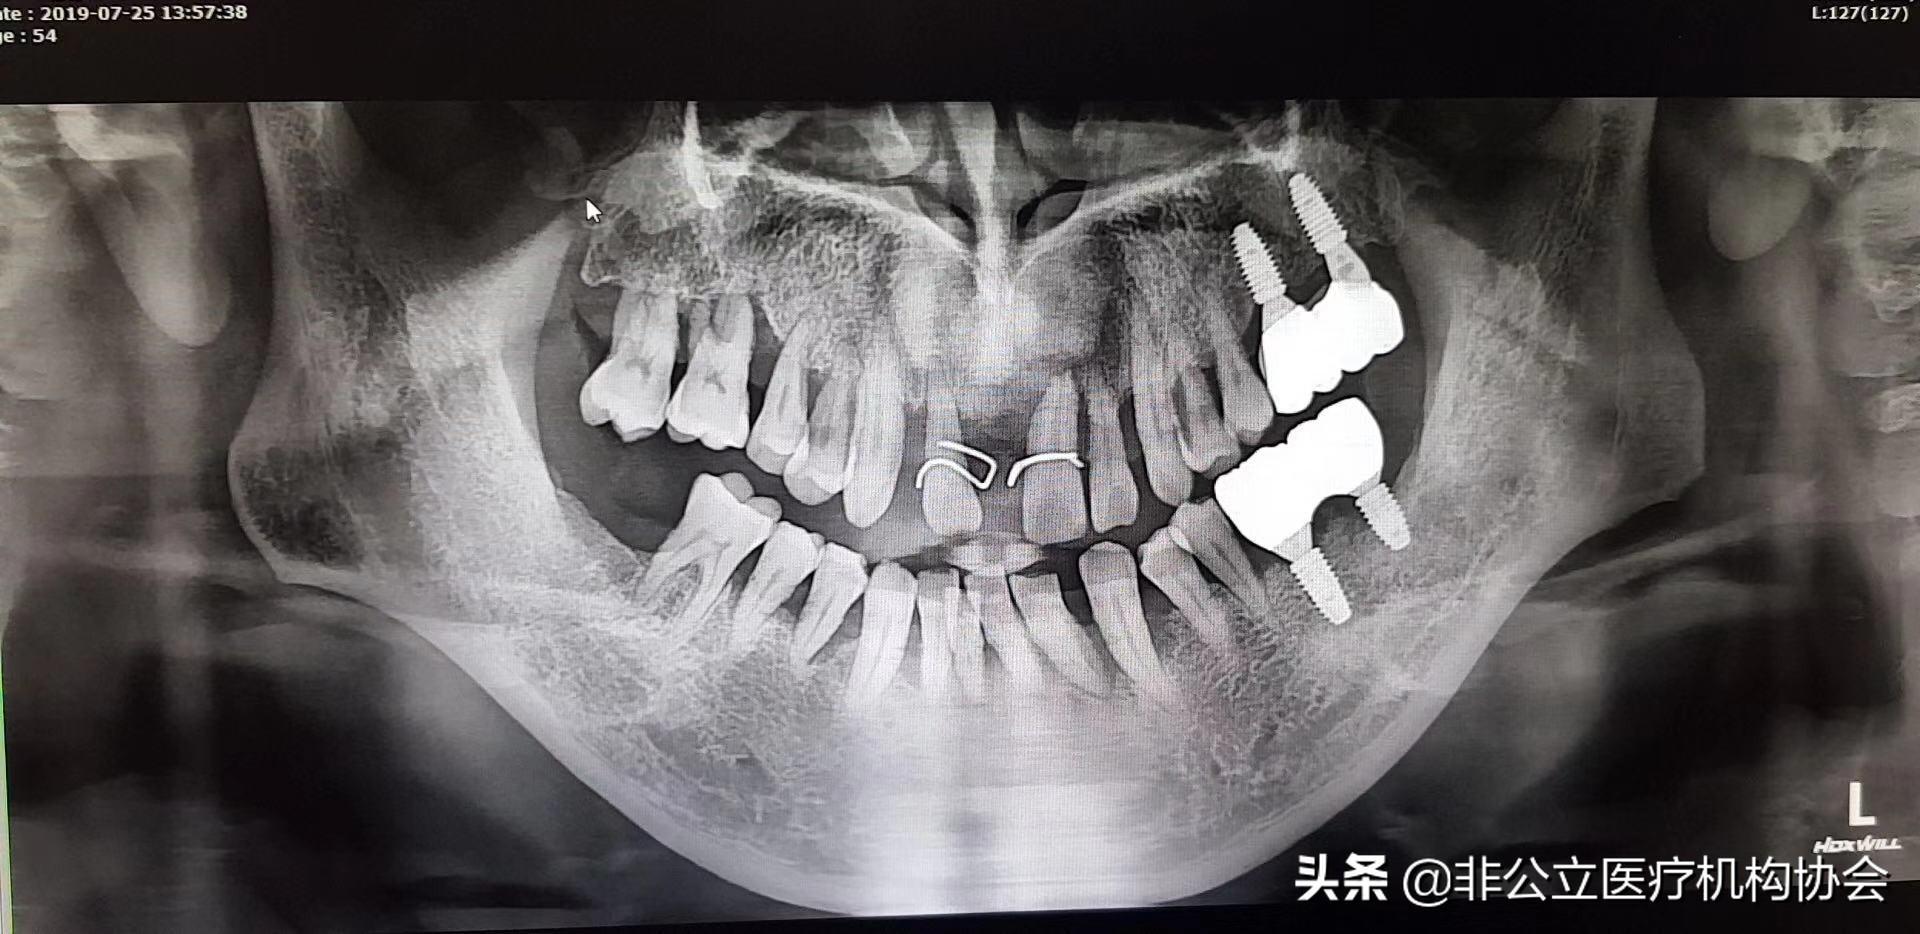

【此病例分為兩部分,這是第一部分】術前的X光片,54歲男,種四顆了,上下前牙。上下前牙牙周病了((一)

術前消毒(二)

檢查:上下1、23度松動,排列不齊,牙石2度?,牙齦紅腫,輕探出血,CT 檢查水平吸收達根長1/3左右。有牙槽骨吸收。嚴重牙周病。